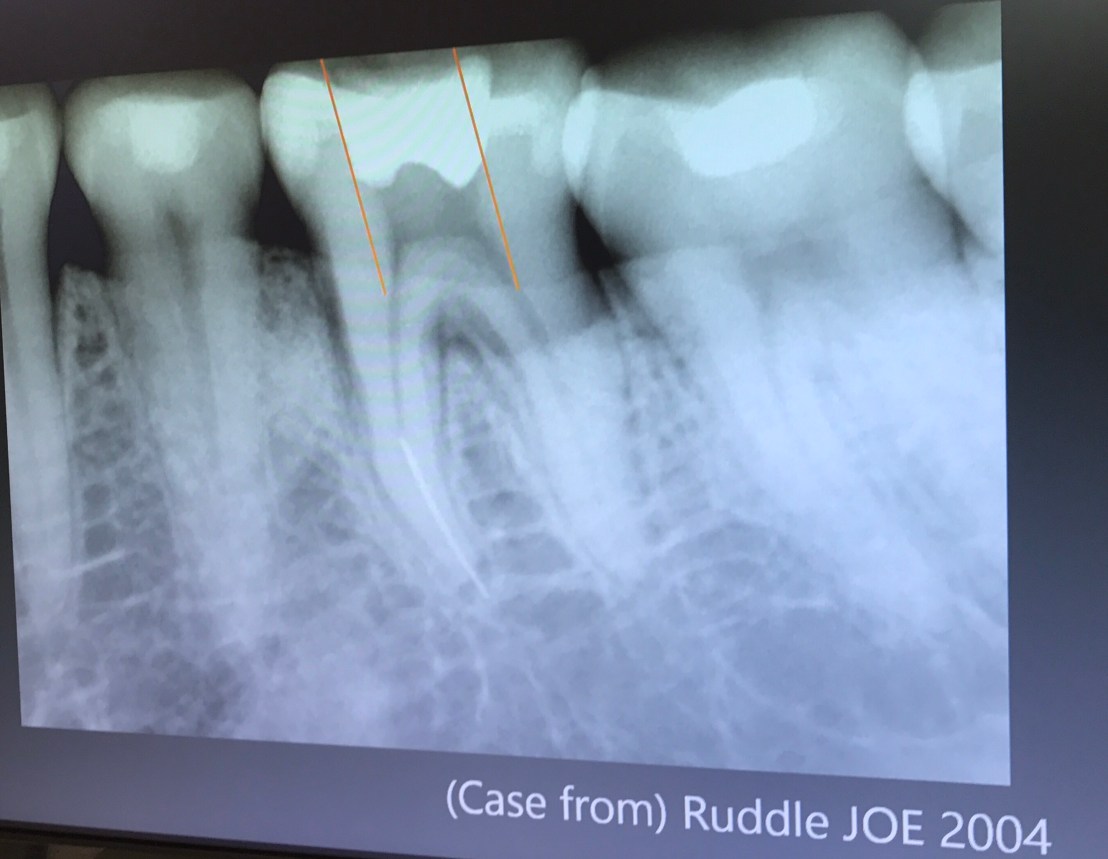

ลองสังเกตเส้นที่ลาก ตำแหน่งของ MB2 จะอยู่ mesial ต่อเส้นนี้ที่ระยะประมาณ 1-2.5 มม.

แนวเส้นประสีแดง คือ บริเวณที่จะพบ MB2